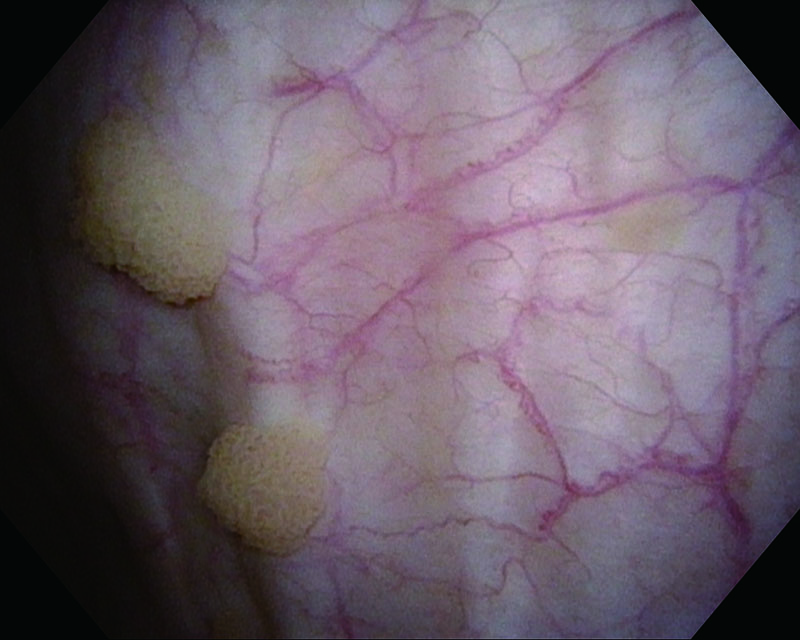

Rubor mucosa, age 81, male

White Light

NBI™ Technology

Histology UC, CIS

Comments

The case suspected carcinoma in situ and identified rubor bladder mucosa. Histopathologic examination revealed CIS.